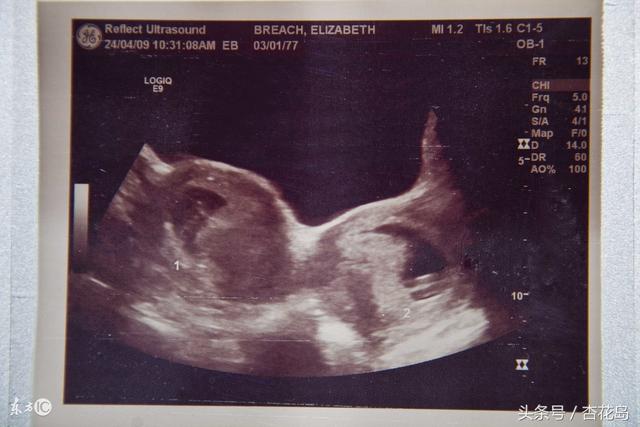

双子宫的情况不多见,在医院很少碰见,一是因为这是种子宫畸形,异常情况毕竟是少数,二是双子宫很难被发现,因为患者平时没有什么特殊表现,一般是在体检双子宫是怎么回事、做人流术、孕前检查或分娩时不经意的发现。双侧子宫同时妊娠的状况很少见,但也会有,称为双卵受精。

双子宫中单侧子宫怀孕,另一侧子宫也会有变化,在怀孕早期内分泌激素变化较大,两侧子宫都会受其影响尤其是雌激素的影响,体积都会增大,之后怀孕侧子宫会因宫腔内压力继续增大,未孕侧子宫增大不会很明显。未孕侧子宫也会有蜕膜的改变,而且怀孕期间孕激素水平会升高,所以未孕侧子宫也不会有月经血,两侧子宫宫颈都会在激素的影响下充血、水肿,宫颈管内腺体增生、肥大,使宫颈管自妊娠早期慢慢变软,在妊娠期宫颈会一直关闭到足月生产时。

双子宫会增加流产风险,早期做人流,由于失误会误刮未孕侧子宫的情况很难避免,导致孕侧子宫的胚胎未刮,妊娠继续。妊娠晚期可能会由于胎位不正常,顺产时未孕侧子宫会妨碍最先进入骨盆的胎儿部分,造成不能顺产,导致了剖宫产率的增加。在健康成为时代主题的大环境下,体检成为常态,双子宫也没有那么难发现,一旦发现自己是双子宫,在有怀孕的需求时,注意孕期安全及生产安全。